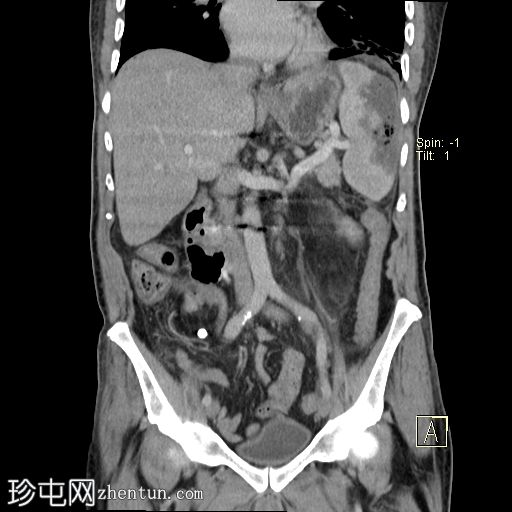

冠状C+门静脉期

脾脏肿大,可见一个边界不清的大型包膜下积液,内有多个大气泡,提示脓肿已延伸至腹腔,导致气腹。

左侧肾旁筋膜反应性增厚,伴有肾周脂肪条带。

左

肺

下叶可见一片实变或肺不张。